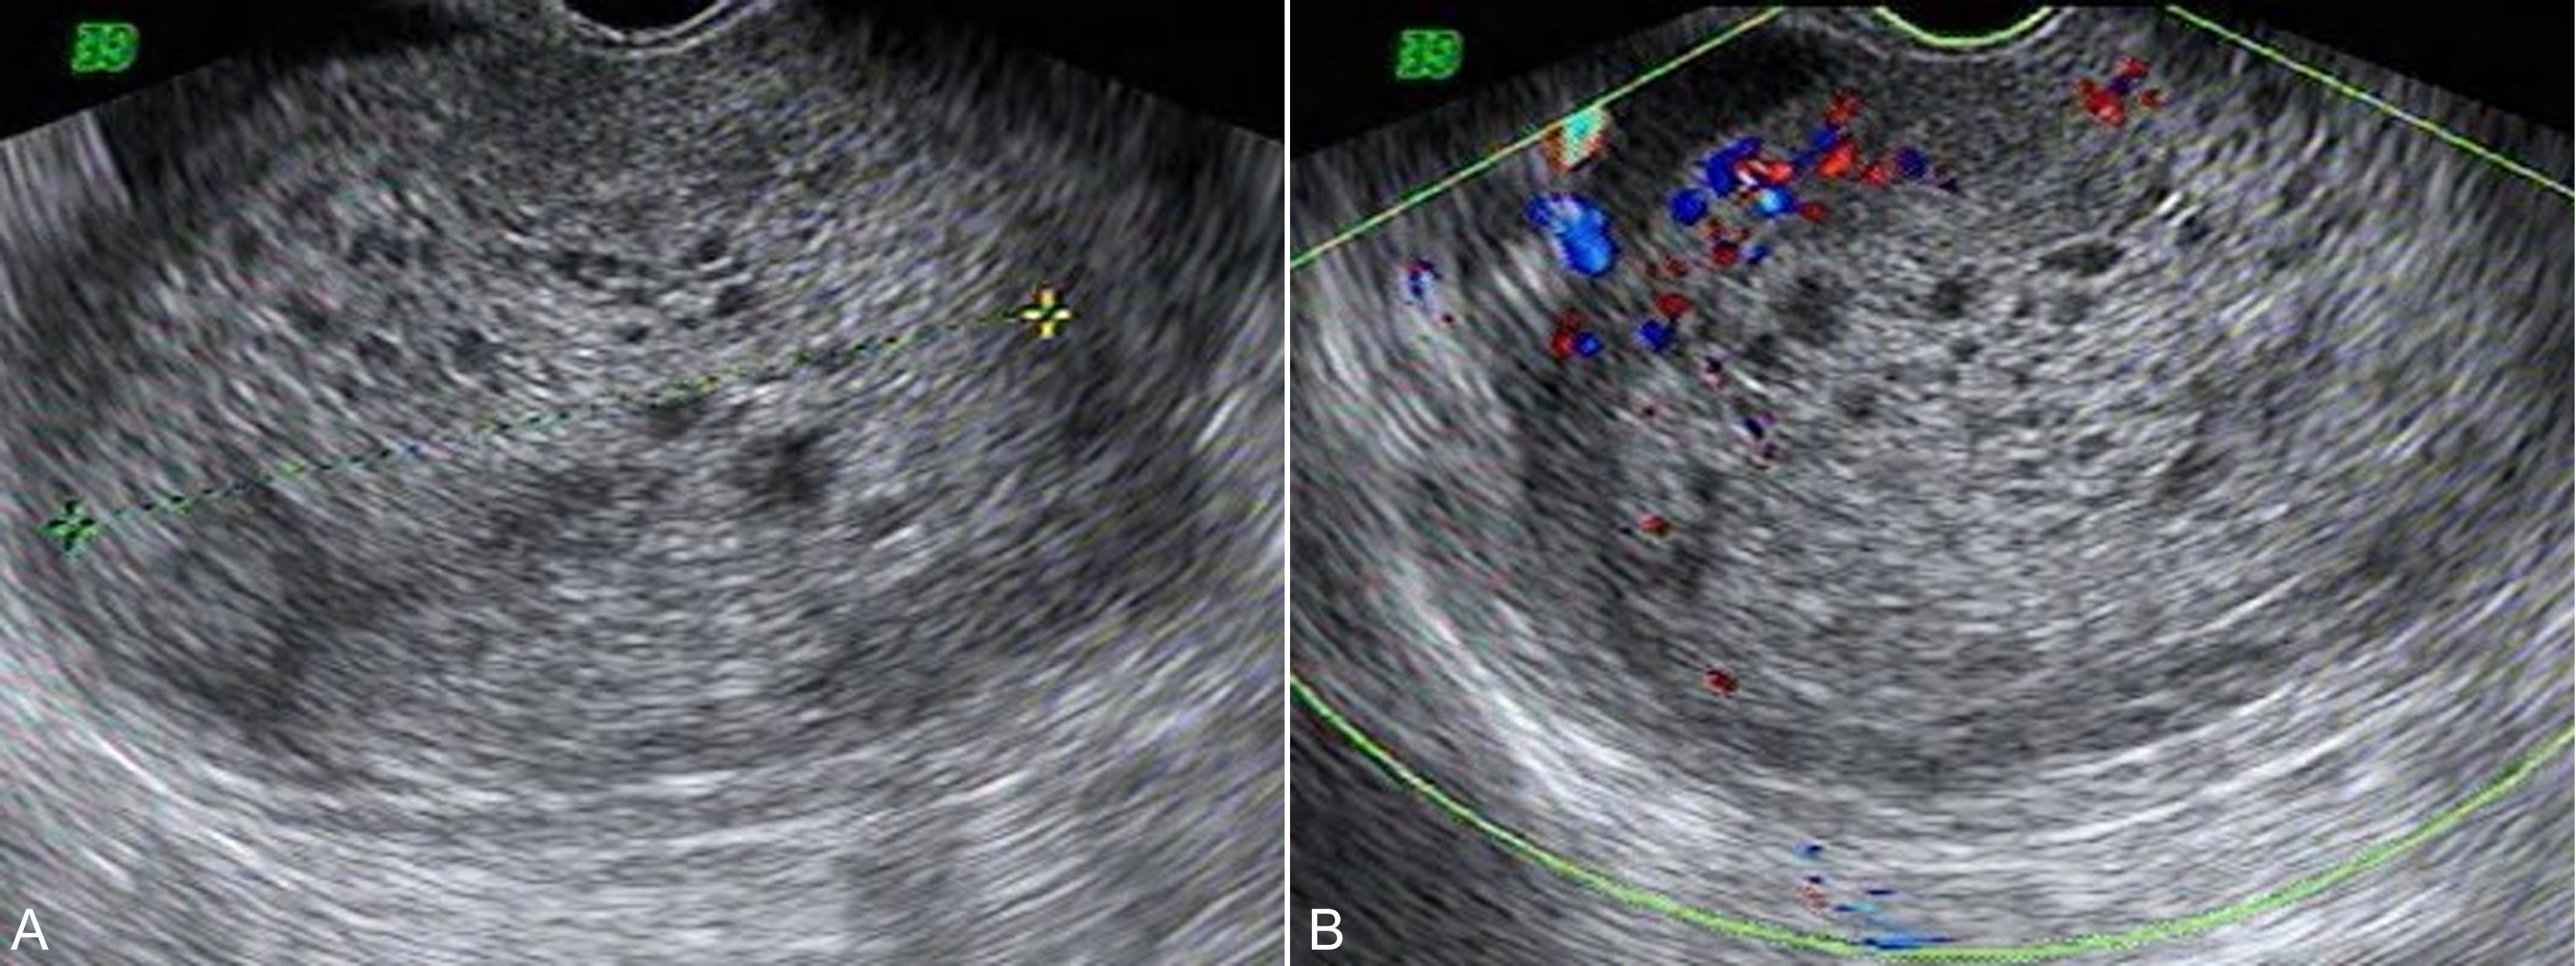

图3葡萄胎声像图

彩色多普勒血流显像检查可以发现子宫动脉及子宫壁血流明显加速,舒张期血流速度明显加快,形成典型的低阻力血流频谱(图4);随着治疗的好转局部血流逐渐减少,血流阻力逐渐升高恢复正常。以彩色多普勒能量图检查可以更为敏感地显示丰富的血流。经阴道彩色多普勒超声检查可以获得更好的图像分辨率和敏感的血流显示;三维超声检查可以重建子宫内病变的形态及其血管空间结构,对病变的评估复查更帮助。

图4葡萄胎水泡状组织周围及子宫壁血流增多及低阻力型血流速度曲线